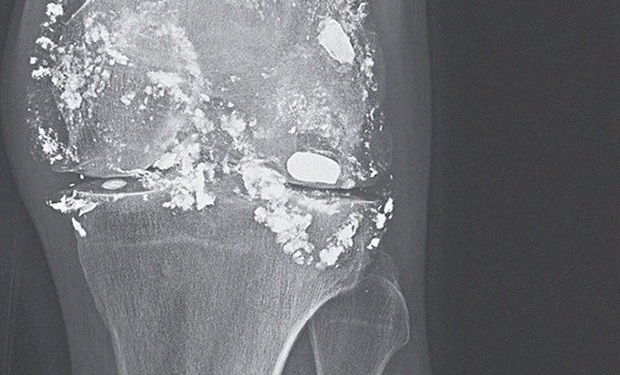

14 лет назад пуля застряла в кости и хирурги решили ее не вытаскивать. После того, как мужчина снова обратился за помощью из-за хронической боли в колене, ему еще раз сделали рентгенографию. Оказалось, что на протяжении этих лет пуля распалась на части, которые остались в тканях коленного сустава.

Слева – пуля, которая застряла 14 лет назад, справа – пуля, который частично распалась

Как следствие этого – скопление большого количества жидкости. Медики отметили, что в теле мужчины обнаружили повышенное содержание свинца и анемию, которая сопровождает отравление свинцом.

Колено пациента после распада пули на свинец